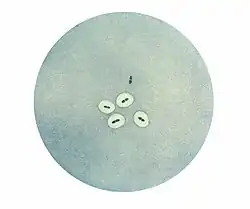

Reacción de Quellung

Luego, durante la primera década del siglo XX y mediante el empleo de técnicas inmunológicas, Neufeld descubrió que había tres tipos de neumococo y describió por primera vez la diferenciación de los neumococos en serotipos sobre la base de antisueros específicos de cada tipo. En presencia de antisuero de tipo I los neumococos de tipo I se hinchaban y los de tipos II y III también lo hacían en presencia de sus antisueros específicos. Neufeld llamó a esta prueba reacción de Quellung (término alemán que significa hinchazón). La primera descripción de serotipos de neumococo fue publicada por Neufeld en 1902.[8][9] La reacción de Quellung facilitó la identificación de laboratorio de los tipos de neumococo.[10] Sobre la base de los descubrimientos de Neufeld Fred Griffith demostró que los neumococos podían transferir información genética y transformar un tipo en otro[11] y luego Oswald Avery descubrió que la sustancia transformante era el ADN. Toda la biología molecular moderna se ha desarrollado a partir de este trabajo.